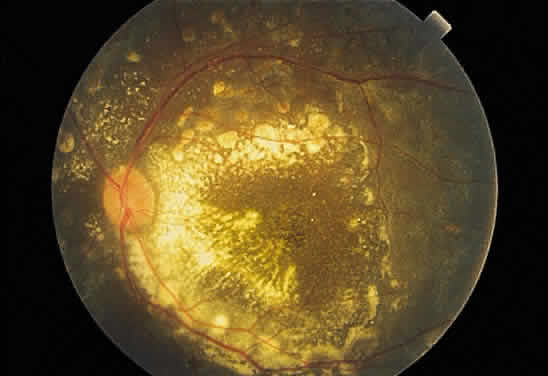

In contrast to lattice degeneration, which affects the inner retinal layers, paving stone degeneration (cobblestone degeneration, peripheral chorioretinal degeneration) affects the outer retinal layers.24 Ophthalmoscopically, paving stone lesions appear as well-demarcated concave zones of depigmentation (Fig. 62A and B). Frequently, the depigmentation is so marked that the larger, outermost choroidal vessels may be seen running through the lesion. The lesions usually are located just posterior to the ora serrata. These depigmented zones may appear individually or may coalesce into larger lesions that demonstrate a scalloped border with pigmented edges.

Fig. 62. A. Paving stones just anterior to the ora serrata. (William Benson: Wills Eye Atlas of Ophthalmology, Fig. 4-58. Philadelphia, Lippincott-Raven, 1996) B. Photograph of the calottes of an autopsy eye showing paving stone degeneration. C. Photomicrograph of paving stone degeneration. The vitreous (v) and choroid (c) are marked for orientation. The retina is detached by an artifact, except in the zone of the paving stone lesion. Notice that the photoreceptors are present to either side of the lesion but not within the lesion. The pigment epithelium also is absent in the area of the lesion. The ophthalmoscopist therefore looks through transparent retina onto choroid and sclera, which accounts for the color of the paving stone lesion.

Histologically, there is loss of the outer retinal layers, including the retinal pigment epithelium (see Fig. 62C). The loss of pigment epithelium accounts for the color of the lesion and permits the larger choroidal vessels to be viewed ophthalmoscopically. The thinned neurosensory retina is firmly adherent to underlying Bruch's membrane and to the reactive pigment epithelium at the margins of the lesion. The pigment epithelial changes account for the clinically observed black border of these zones. Unlike retinal lattice degeneration, there is no change in the overlying vitreous and no pathogenic relation to retinal detachment. In fact, the histopathologic appearance of paving stone degeneration resembles the chorio-retinal adhesion seen after therapeutic cryopexy. The forward advance of a retinal detachment does not extend beyond the posterior edge of a paving stone lesion.